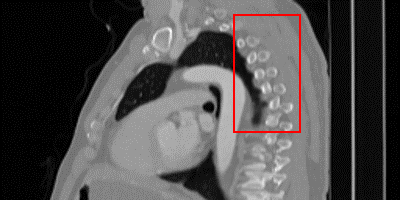

\stackanchorCase 1

\stackanchorHRPSNR/SSIM

\stackanchorDA-VSR37.56/0.971

\stackanchorDA-VSRNAsubscriptDA-VSR𝑁𝐴\textrm{DA-VSR}_{NA}37.02/0.968

\stackanchorSAINT36.89/0.966

\stackanchorSMORE35.99/0.960

\stackanchor3DRDN36.40/0.962

\stackanchor3DRCAN36.54/0.962

\stackanchorBicubic32.49/0.915

Figure 2: Visual comparisons of DA-VSR and other state-of-the-art implementations from the sagittal plane, highlight regions are contrast-adjusted. Case 1 is from the Colon dataset, Case 2 and 3 are from the Kidney dataset[7]. In particular, Case 3 is a lung region cropped from a kidney-containing image. Please refer to the supplemental material for more visual comparisons.

While metrics like PSNR and SSIM are useful to understand performance in aggregate, they can often be too coarse. Domain drift does not happen uniformly on a CT image. Some patches do not suffer as much since similar patches can be observed in the training set, leading to similar overall PSNR metrics; however, some patches suffer heavily due to lack of observations. We provide visualization on SR results, as shown in Fig. 2, to better show where improvements are most often observed. We observe that supervised techniques without adaptation can lead to significant overfitting issues over unseen test sets and create unfaithful details, as seen in Case 2 of Fig. 2 and indicated by the orange arrows. Compared to supervised methods, SMORE produces results that are smoother and more similar to the groundtruth if those patterns are seen in axial slices. For organs that exhibit different patterns between axial and other axes, such as the sagittal spinal structure, SMORE can generate unreliable or overly smooth patterns, as shown in Case 1 of Fig. 2. In comparison, since DA-VSR goes through supervised training on a lung dataset, which contains both LR and HR spine patterns, we observe that it performs much better than SMORE even with adaptation. Interestingly, we also observe improvements over the few unseen cases where a region of lung is included, e.g. in Case 3, by using our proposed adaptation stage. Despite being trained on the lung dataset, other supervised methods still experience local discontinuity over small scale bone structures. In this case, SMORE generates smoother but less structurally reliable details. DA-VSR takes the advantages of both approaches and generate smoother and more reliable details under this challenging case. As no two individuals are the same, DA-VSR’s ability to reduce minor distribution differences can be valuable in real SR applications.